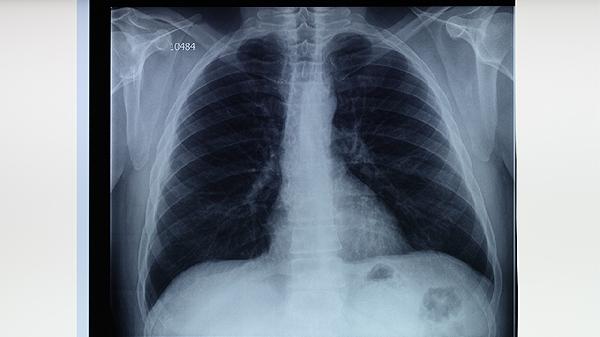

胸部X線能顯示肺部特征性改變?nèi)鐫B出性病灶、纖維鈣化灶或空洞形成。早期肺結(jié)核可能僅表現(xiàn)為肺尖部小片狀陰影,隨著病情進(jìn)展可出現(xiàn)典型的上葉尖后段或下葉背段病變。該檢查對(duì)發(fā)現(xiàn)無(wú)癥狀感染者具有重要價(jià)值,但需注意與肺炎、肺癌等疾病進(jìn)行鑒別。